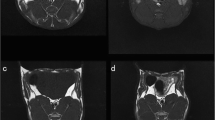

Primary DCE-MRI data were analyzed using vendor-offered DCE post-processing software (Omni Kinetics, GE Healthcare). First, pre-contrast LAVA series with flip angles of 6°, 9°, and 12° were used to calculate pixel-wise T1 maps to obtain pre-contrast tissue longitudinal relaxation time. This measurement was used to convert the signal intensity units into units of contrast agent concentration. Second, the corrected 35-phase enhanced images were imported into the software. A dual-compartment extended Tofts linear model was selected to fit lumbar vertebrae 5–7 in rabbits. A circular ROI was placed in the center of the abdominal aorta to obtain the time-concentration curve as the arterial input function. The brightest phase of the lumbar central level image was selected, and the ROI was manually outlined for lumbar vertebrae 5–7, while avoiding the endplate, intervertebral disc area, vertebral venous plexus, and cerebrospinal fluid (Fig. 1). Quantitative permeability parameters, including volume transfer constant (Ktrans), rate constant (Kep), extravascular extracellular space volume fraction (Ve), and plasma volume fraction(Vp) were calculated.

Sagittal T1WI (a), T2WI (b), and FF (c) images of a rabbit from the diabetic group obtained at the 16th week. The ROIs (red outline) show the L7 vertebral body. DCE-MR image (d), Ktrans map (e), Kep map (f), Ve map (g), and Vp map (h) of a rabbit from the diabetic group obtained at the 16th week. ROIs (red outline) show the L5–7 vertebral body

Quantitative permeability parameters from the ROIs of lumbar vertebrae 5–7 were calculated based on Ktrans, rate constant (Kep), extravascular extracellular space volume fraction (Ve) and plasma volume fraction (Vp) maps shown in Fig. 1. The Ktrans map were imported into the software (Omni Kinetics, GE Healthcare) to automatically extract 76 texture features, including grayscale histogram feature, gray level co-occurrence matrix features and gray-level run length matrix.IDEAL-IQ scan images were imported into the AW4.6 workstation (GE Healthcare). The fat fraction (FF) ratio from regions of interest (ROIs) of lumbar vertebrae 5–7 was calculated using the IDEAL IQ FF map shown in Fig. 1.